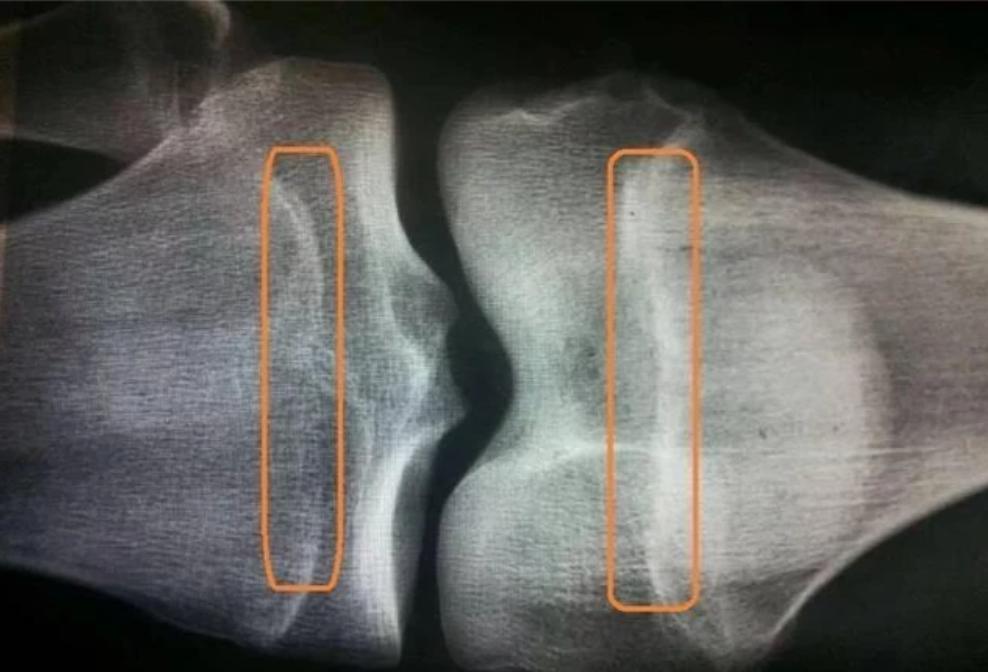

孩子什么时候不长个,不在于孩子年龄多大,也不在于他现在多高,最重要的是看孩子骨骺线闭合没有。

有太多家长出于晚长、23窜一窜的思想,对孩子身高不是太在意,结果到成年发现不长想干预的时候,骨骺线却闭合了,一点长高空间都没有!

遵循3岁以下不查、3岁以上1年1次、青春期半年1次的频率去监测骨龄。

这样做的目的是为了准确掌握骨龄进展情况,防止出现骨龄已经偏大而自己却不知道的情况出现。

如果在监测过程中,家长发现孩子骨龄大了,大1岁以内的不用慌张,属于正常现象[青春期的孩子要当心], 大1岁以上的,首先运用中医中药延缓干预,比如中成药知柏,滋阴泄火类方剂等等,都有很好的效果。

如果孩子骨龄偏大,且骨龄自身已经很大了的,中医中药抑制不理想的时候,就要考虑西医抑制针了,但打上以后,也要跟上促长的措施,不然骨龄是拉住了,身高增长同时也拉住了,骨龄不跑,身高也不长。

咱们按拍一次150来算,到孩子生长发育结束前,15年下来,骨龄评测的总花费,最高在3000元以内。